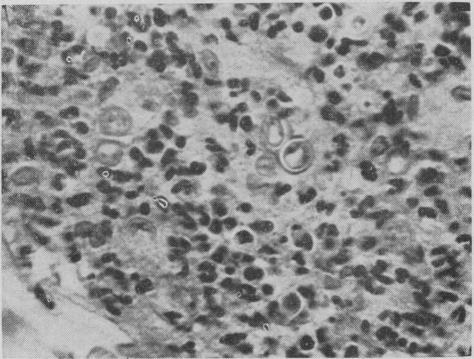

GRANDBOIS J

Can Med Assoc J. 1958 Nov 15;79(10):828-32.